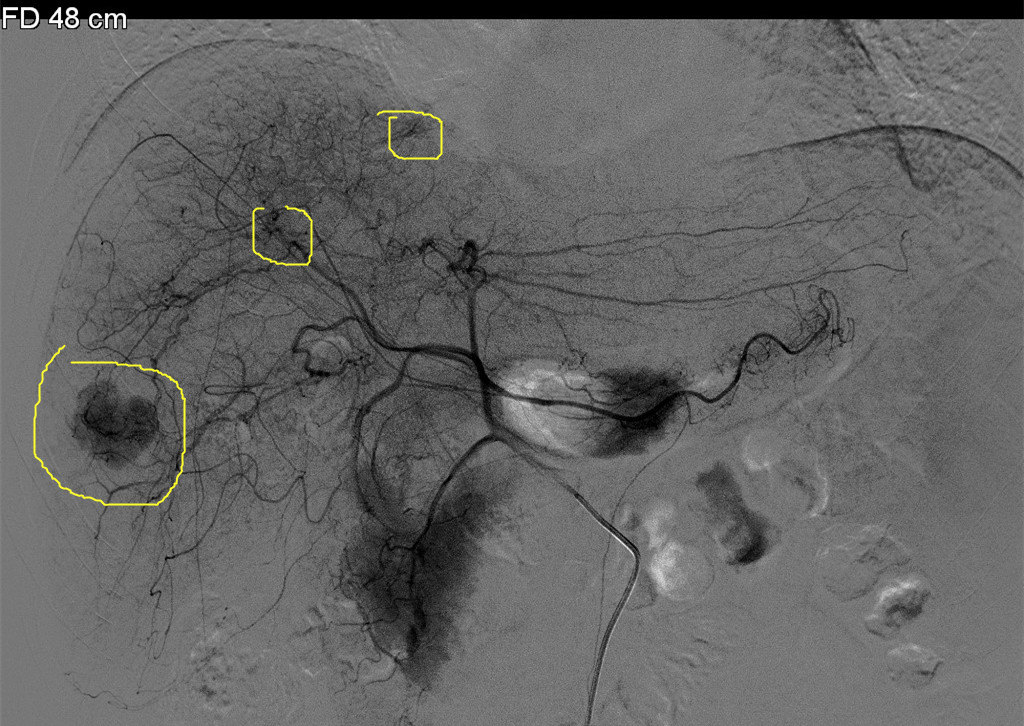

术前必须搞明白,立马做DSA,果真发现另外两个微小病灶,一个在8段,一个在5段,随即做了TACE,将三个病灶全部栓塞。一周后在CT引导下我用射频将三个病灶全部毁损,效果很不错。